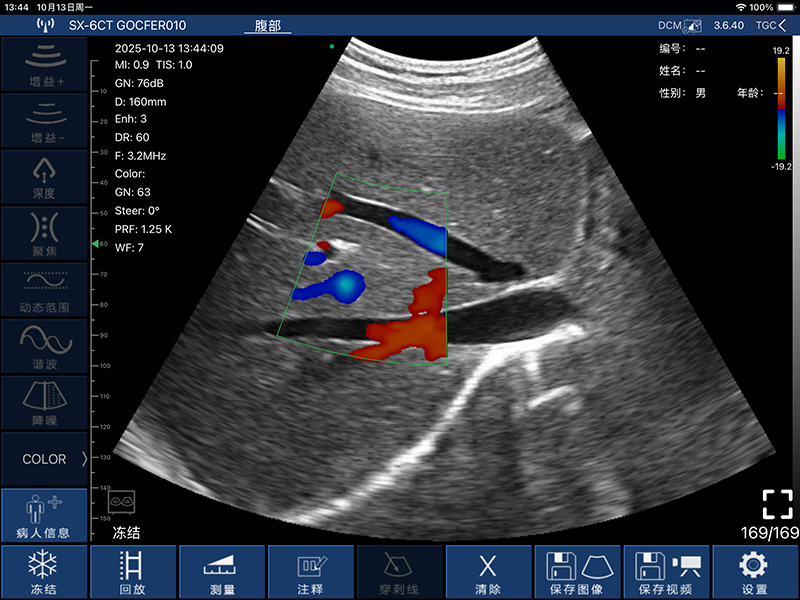

• 频率:凸阵探头3.2MHz/5.0MHz,阵探头7.5MHz/10.0MHz,相控阵探头2.5MHz/5.0MHz

• 深度:凸阵探头90/160/220/305mm,线阵探头20/40/60/80mm,相控阵探头90/120/140/160MM

• 扫描角度和宽度:凸阵探头60°,相控阵探头80°,线阵探头40mm

• 显示模式:B、B/M、Color、PDI、PW